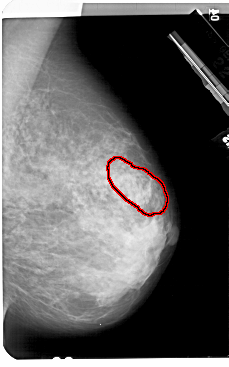

A_1504_1.RIGHT_MLO

RIGHT_MLO LINES 5491 PIXELS_PER_LINE 3421 BITS_PER_PIXEL 12 RESOLUTION 43.5 OVERLAY

FILE: A_1504_1.RIGHT_MLO.OVERLAY

TOTAL_ABNORMALITIES 1

ABNORMALITY 1

LESION_TYPE MASS SHAPE ARCHITECTURAL_DISTORTION MARGINS SPICULATED

ASSESSMENT 5

SUBTLETY 3

PATHOLOGY MALIGNANT

TOTAL_OUTLINES 1

BOUNDARY